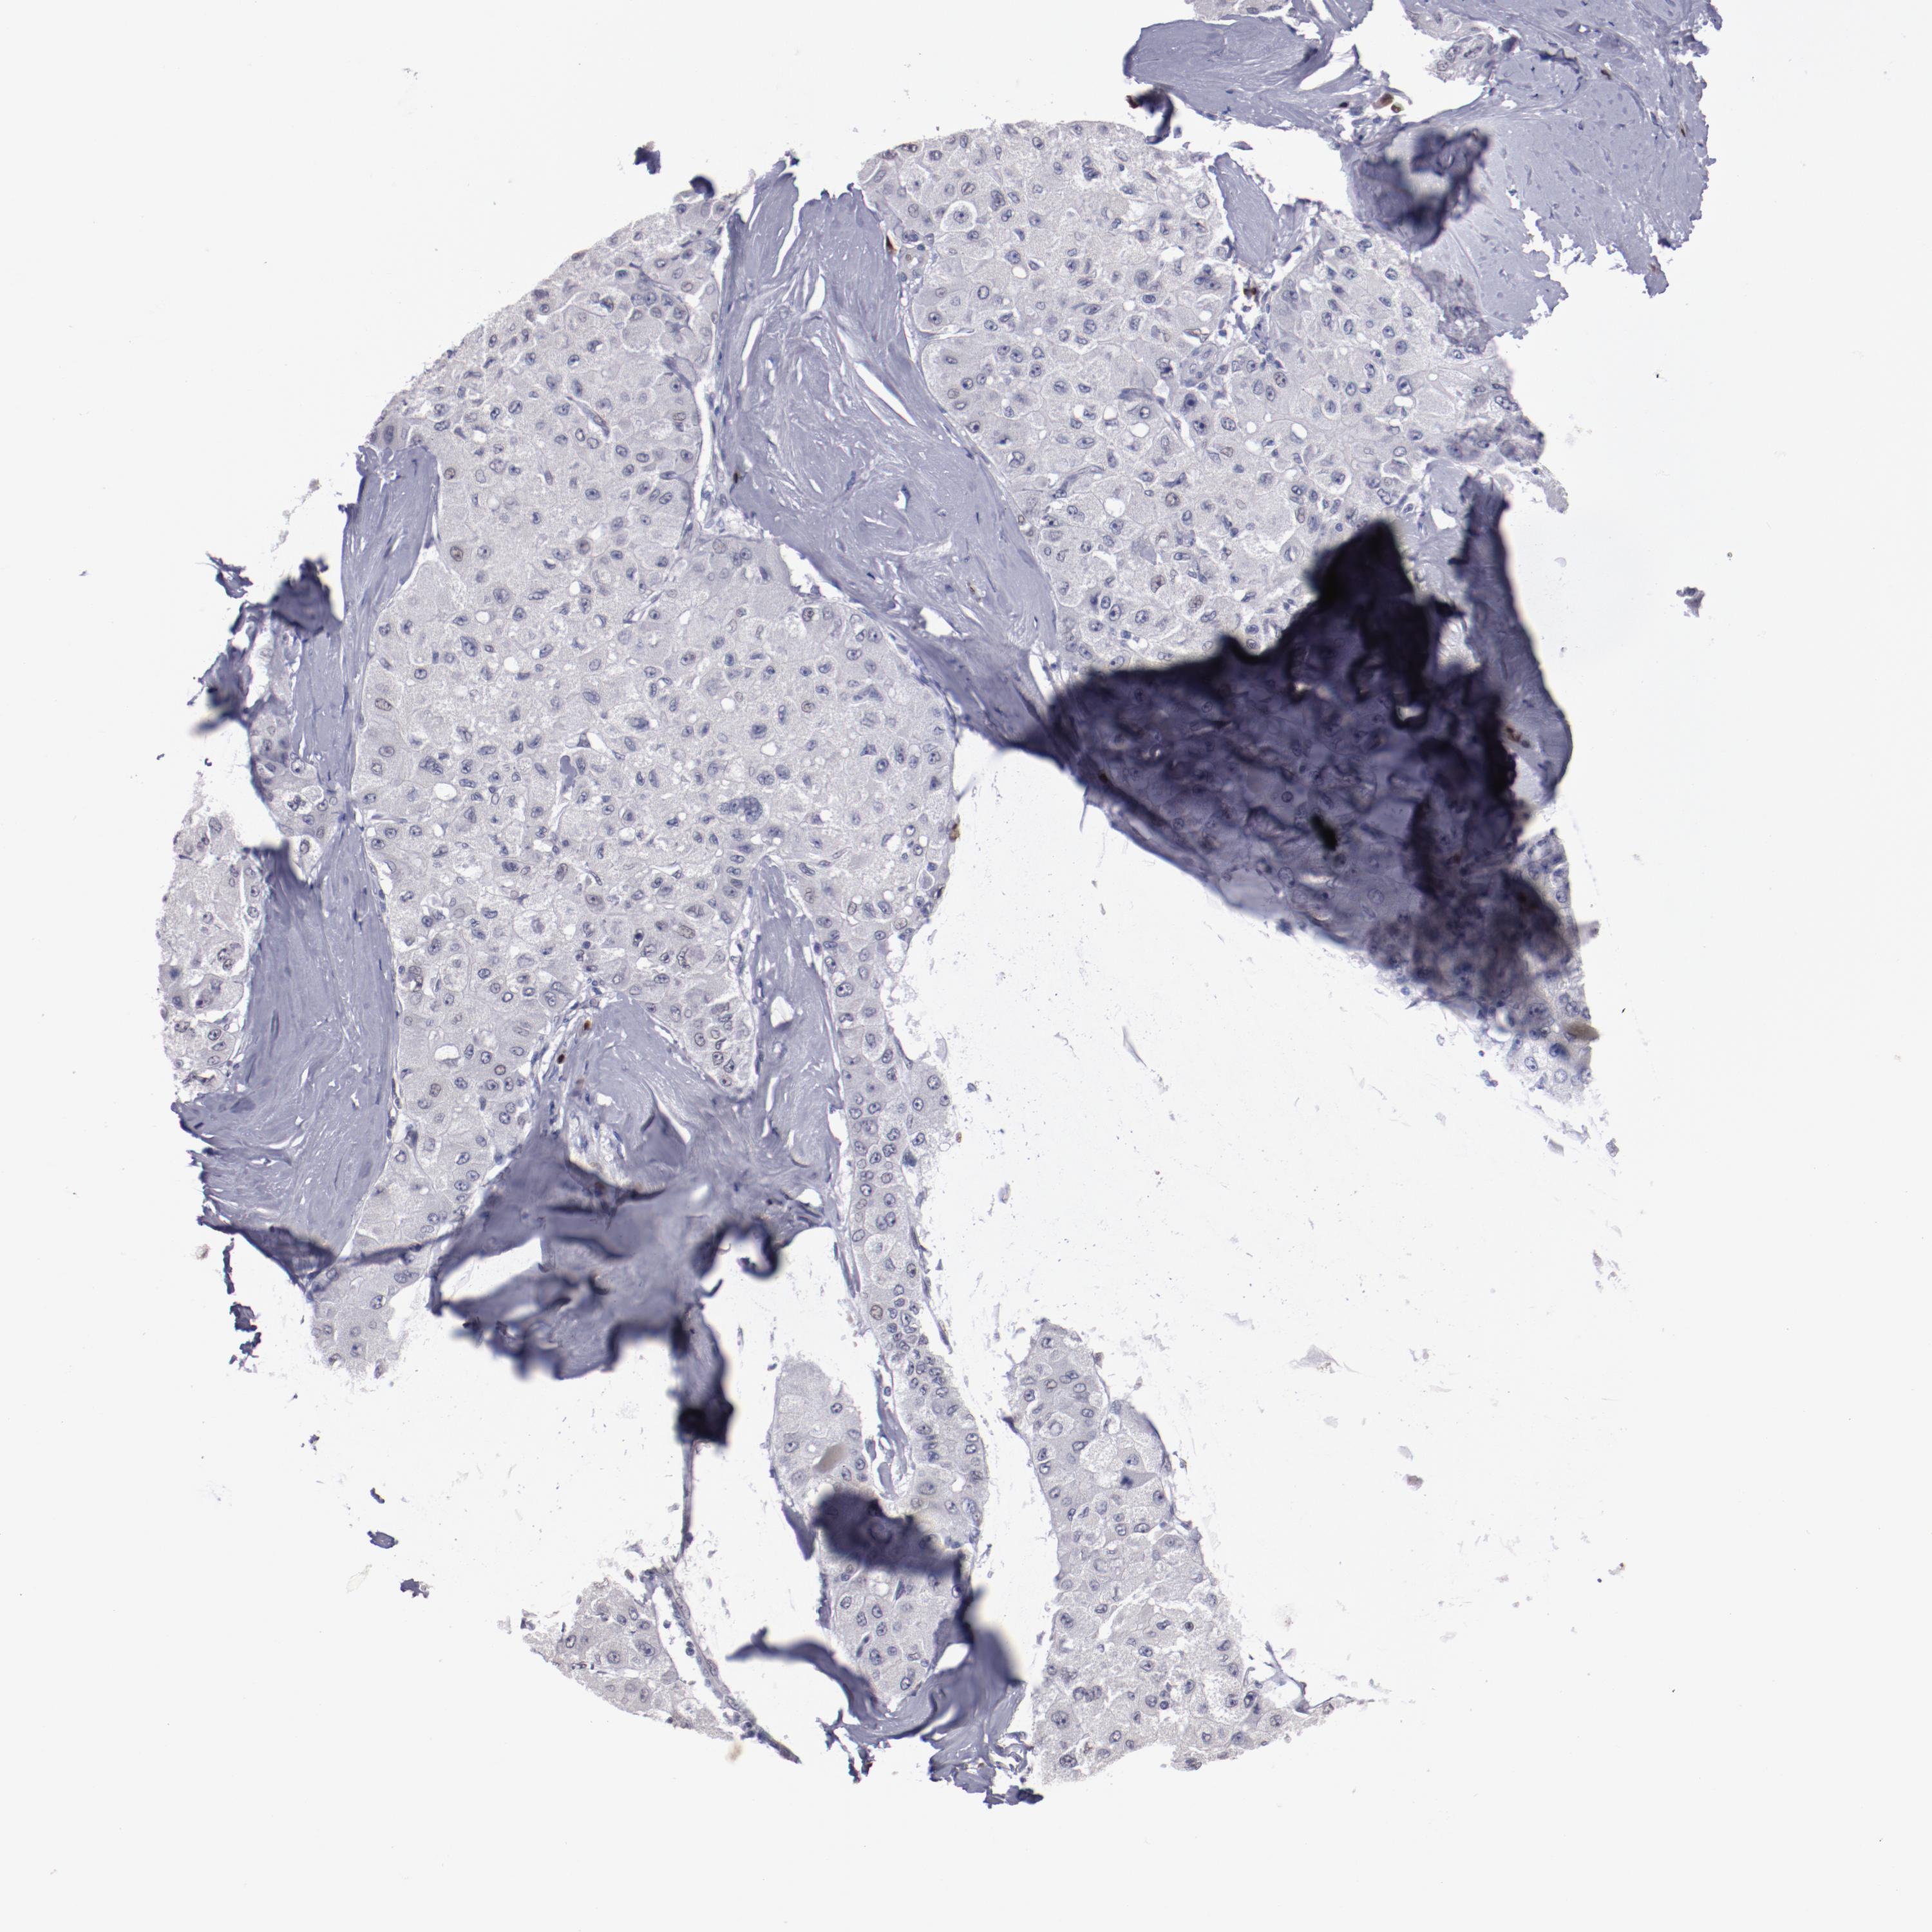

LIVER CANCER - Protein expressioni

A mouse-over function shows sample information and annotation data. Click on an image to view it in a full screen mode. Samples can be filtered based on level of antibody staining by selecting one or several of the following categories: high, medium, low and not detected. The assay and annotation is described here.

Note that samples used for immunohistochemistry by the Human Protein Atlas do not correspond to samples in the TCGA dataset.

Antibody stainingi

Antibody staining in the annotated cell types in the current human tissue is reported as not detected, low, medium, or high, based on conventional immunohistochemistry profiling in selected tissues. This score is based on the combination of the staining intensity and fraction of stained cells.

Each image is clickable and will lead to virtual microscopy that enables deeper exploration of all samples and also displays staining intensity scores, fraction scores and subcellular localization as well as patient and tissue information for each sample.

Antibody HPA002038

Antibody HPA002698

Antibody CAB013508

Staining

Cholangiocarcinoma

Carcinoma, Hepatocellular, NOS